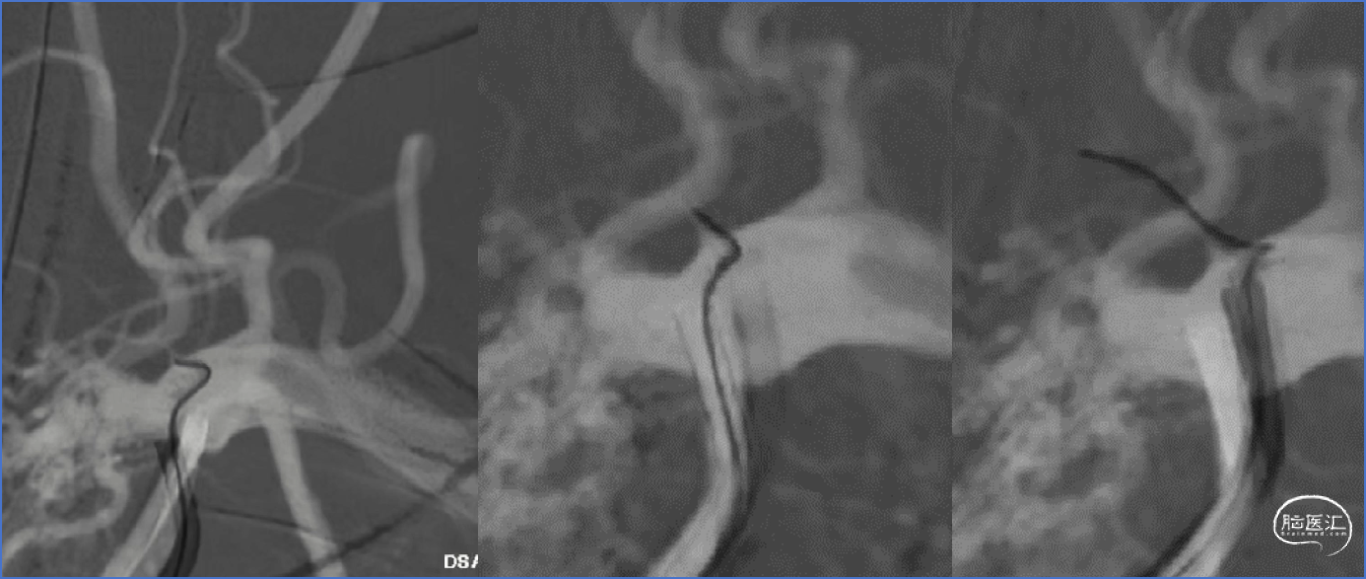

Bridge4.0×15mm球扩支架植入

术后复查正侧位及XperCT

术前术后图像对比